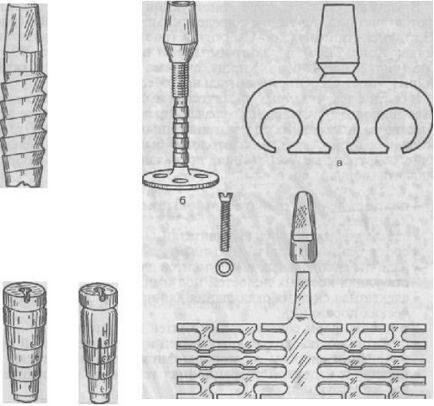

Ábra. 280. reakcióvázlat endodonto enossalnogo-graft (a); X-ray.

4. Endodontic implantátumok (endodonto-enossalnye) - egy csap, és a kimeneten a fejlett elülső fogak gyökércsatorna keresztül apikális lyuk a csont, hogy a mélysége 3-5,5 mm. Ezek szolgálnak rögzítés (sínbe) mobil fogak fogágybetegség. Vnutrikornevaya implantátum felülete is, intraossealis lehet menetes felcsavarozható. Endodonto-enossalnye implantátumok titánból, tantálból, KHS, alumínium-oxid (ábra. 280).

Ábra. 282. implantátumok: hengeres (a); csavart (b).

5. enosszális implantátumok (endossalnye, enossalnye). A standok pillanatnyilag ez a legszélesebb körben használt típusú implantátum. Eltérően más típusú intraossealis implantátumok vannak rögzítve nemcsak mechanikai erők, hanem azért is, mert a osseointegration folyamatot. Különböztesse intraossealis szerinti implantátumok Linkova - lemez (ábra. 281) és Brenemarku - hengeres, csavart (ábra 282.); késedelmes hozzávetőleges, hogy a gyökér a természetes fog formáját legelterjedtebb az orvosi gyakorlatban. A beültetés után az implantátum, ha minden feltétel teljesül, a folyamat osseointegráció kezdődik, azaz implantátum, amely lehet akár hengeres vagy csavarvonal alakú nyílások vagy nélkülük, van rögzítve a csontban nem csak a miatt, hogy az alak, hanem amiatt is, hogy a csontképződést közvetlenül az implantátum felületén „betétek” a csont az implantátum felszínén, és a „végrehajtása „szerkezet a felületén.